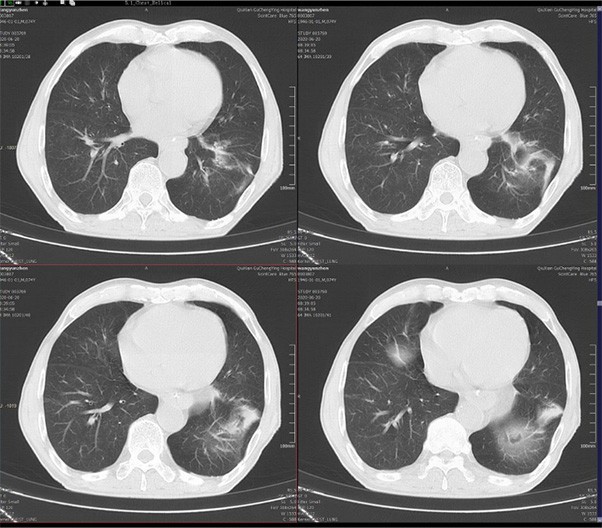

臨床畫廊